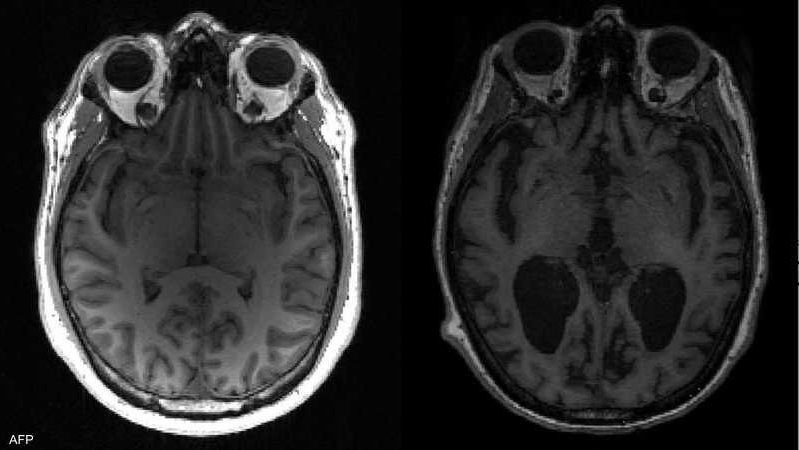

يحدث الخرف بسبب انخفاض تدفق الدم إلى الدماغ، مما يؤدي إلى إتلاف خلايا الدماغ وقتلها في النهاية.

تضييق الأوعية الدموية الصغيرة الموجودة في أعماق الدماغ، والمعروف باسم الخرف الوعائي تحت القشري أو مرض الأوعية الدموية الصغيرة

السكتة الدماغية (حيث ينقطع تدفق الدم إلى جزء من الدماغ فجأة، عادةً بسبب جلطة دموية)، ويُطلق عليها اسم خرف ما بعد السكتة الدماغية أو خرف الاحتشاء الفردي، طبقًا لموقع "Nhs" الطبي.

الكثير من "السكتات الدماغية الصغيرة" (وتسمى أيضًا النوبات الإقفارية العابرة أو TIAs) التي تسبب ضررًا صغيرًا ولكن واسع النطاق للدماغ، ويُعرف باسم الخرف متعدد الاحتشاءات

ويعاني بعض الأشخاص المصابين بالخرف الوعائي أيضًا من تلف في الدماغ ناجم عن مرض الزهايمر، ويعرف هذا بالخرف المختلط.